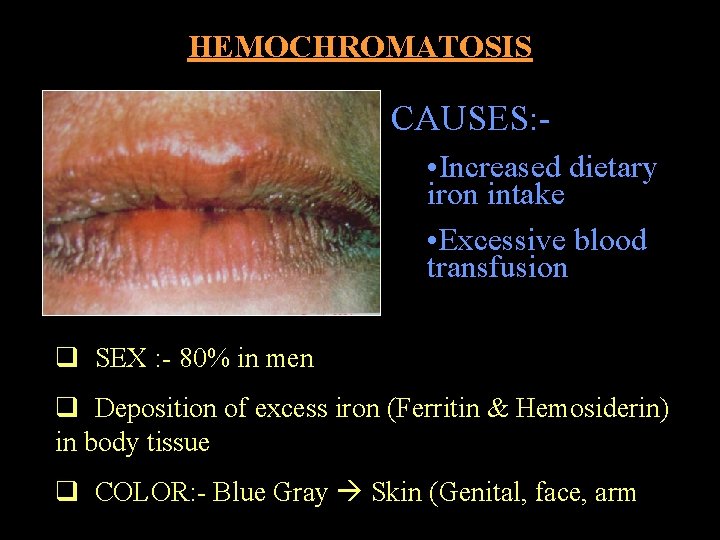

HEMOCHROMATOSIS CAUSES: • Increased dietary iron intake • Excessive blood transfusion q SEX : - 80% in men q Deposition of excess iron (Ferritin & Hemosiderin) in body tissue q COLOR: - Blue Gray Skin (Genital, face, arm